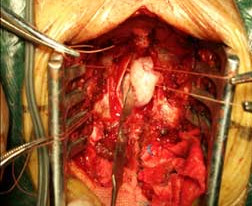

【手術(shù)圖片】

三叉神經(jīng)微血管減壓手術(shù)切口

術(shù)中顯微鏡鏡下神經(jīng)顯露